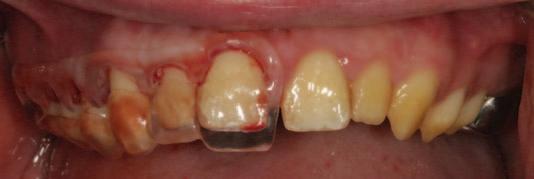

n Following clinical and radiographic assessment of the width of the keratinised mucosa, the positioning of the gingival margin in relation to the cemento-enamel junction (CEJ) and the distance of the CEJ from the bone crest, the surgical guide is tested for stability and the proposed gingival margins are approved ( Figure 3 ). To achieve an optimised outcome, the operator should envisage that at least 2mm of keratinised tissue, including at least 1mm of attached gingivae, remain intact post surgery.4 A favourable crown–root ratio and integrity of furcation anatomy must remain intact post surgery.

n During the surgery, the upper, inner edge of the window within the guide provides the surgeon with the exact site of the proposed definitive gingival margin location and in doing so, indicates the precise location of the initial internal bevel incision (Figures 4A-4C ).5

FIGURE 3: A pre-operative radiographic assessment and clinical try-in of the surgical guide gives the clinician an indication of the extent of crown lengthening surgery required. The clinician may confirm that sufficient crown–root ratio, distance from furcation anatomy, keratinised tissue, and attached gingivae will remain post surgery, and ensure the complete and comfortable seating of the guide at this stage. It is of note that the stainless steel crown on tooth UR6 was lost to retention failure between the radiographic assessment and the clinical assessment in this case.